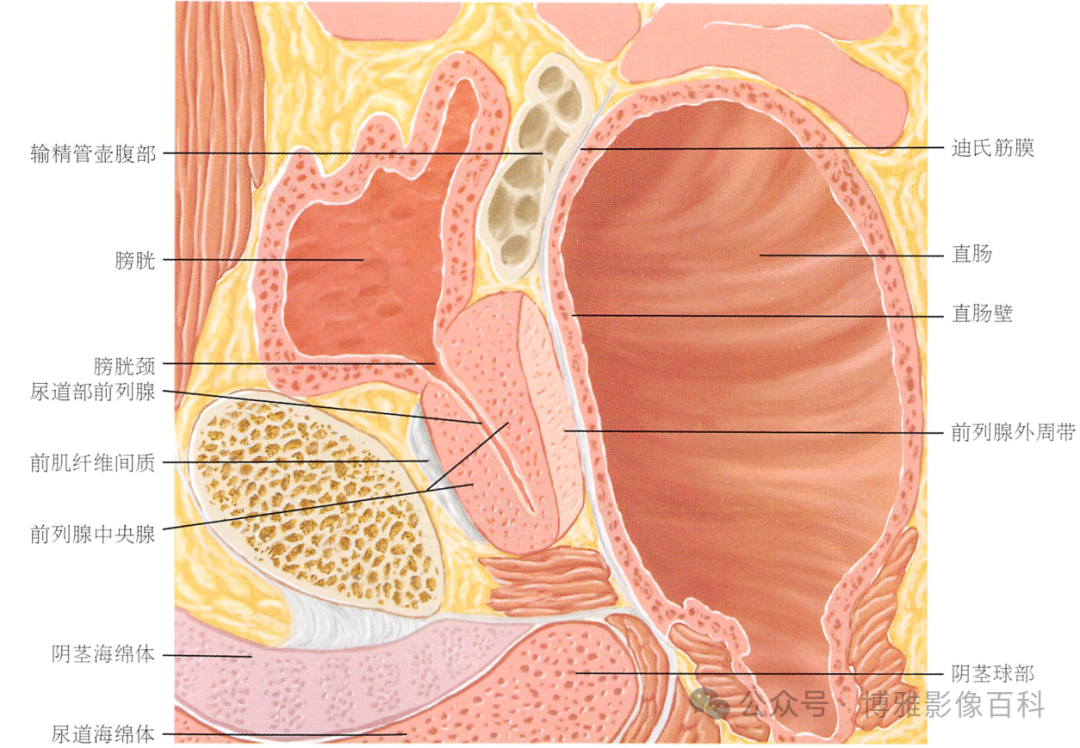

解剖学

前列腺分区解剖学

70-75% 的前列腺癌起源于外周带 (PZ)。该区域的后部可以通过直肠指检进行检查。

25% 的前列腺癌起源于移行带 (TZ)。极少数前列腺癌出现在中央带或前纤维肌基质中。

MR 解剖学

前列腺良性增生患者的轴向T2 图像,其他方面正常。外周带是一薄层均匀的高信号,边界清晰连续性的低信号包膜。移行带通常表现为不均匀中等信号,病灶被边界清楚的BPH良性前列腺增生结节所取代。精囊具有均匀T2高信号。未见淋巴结肿大。